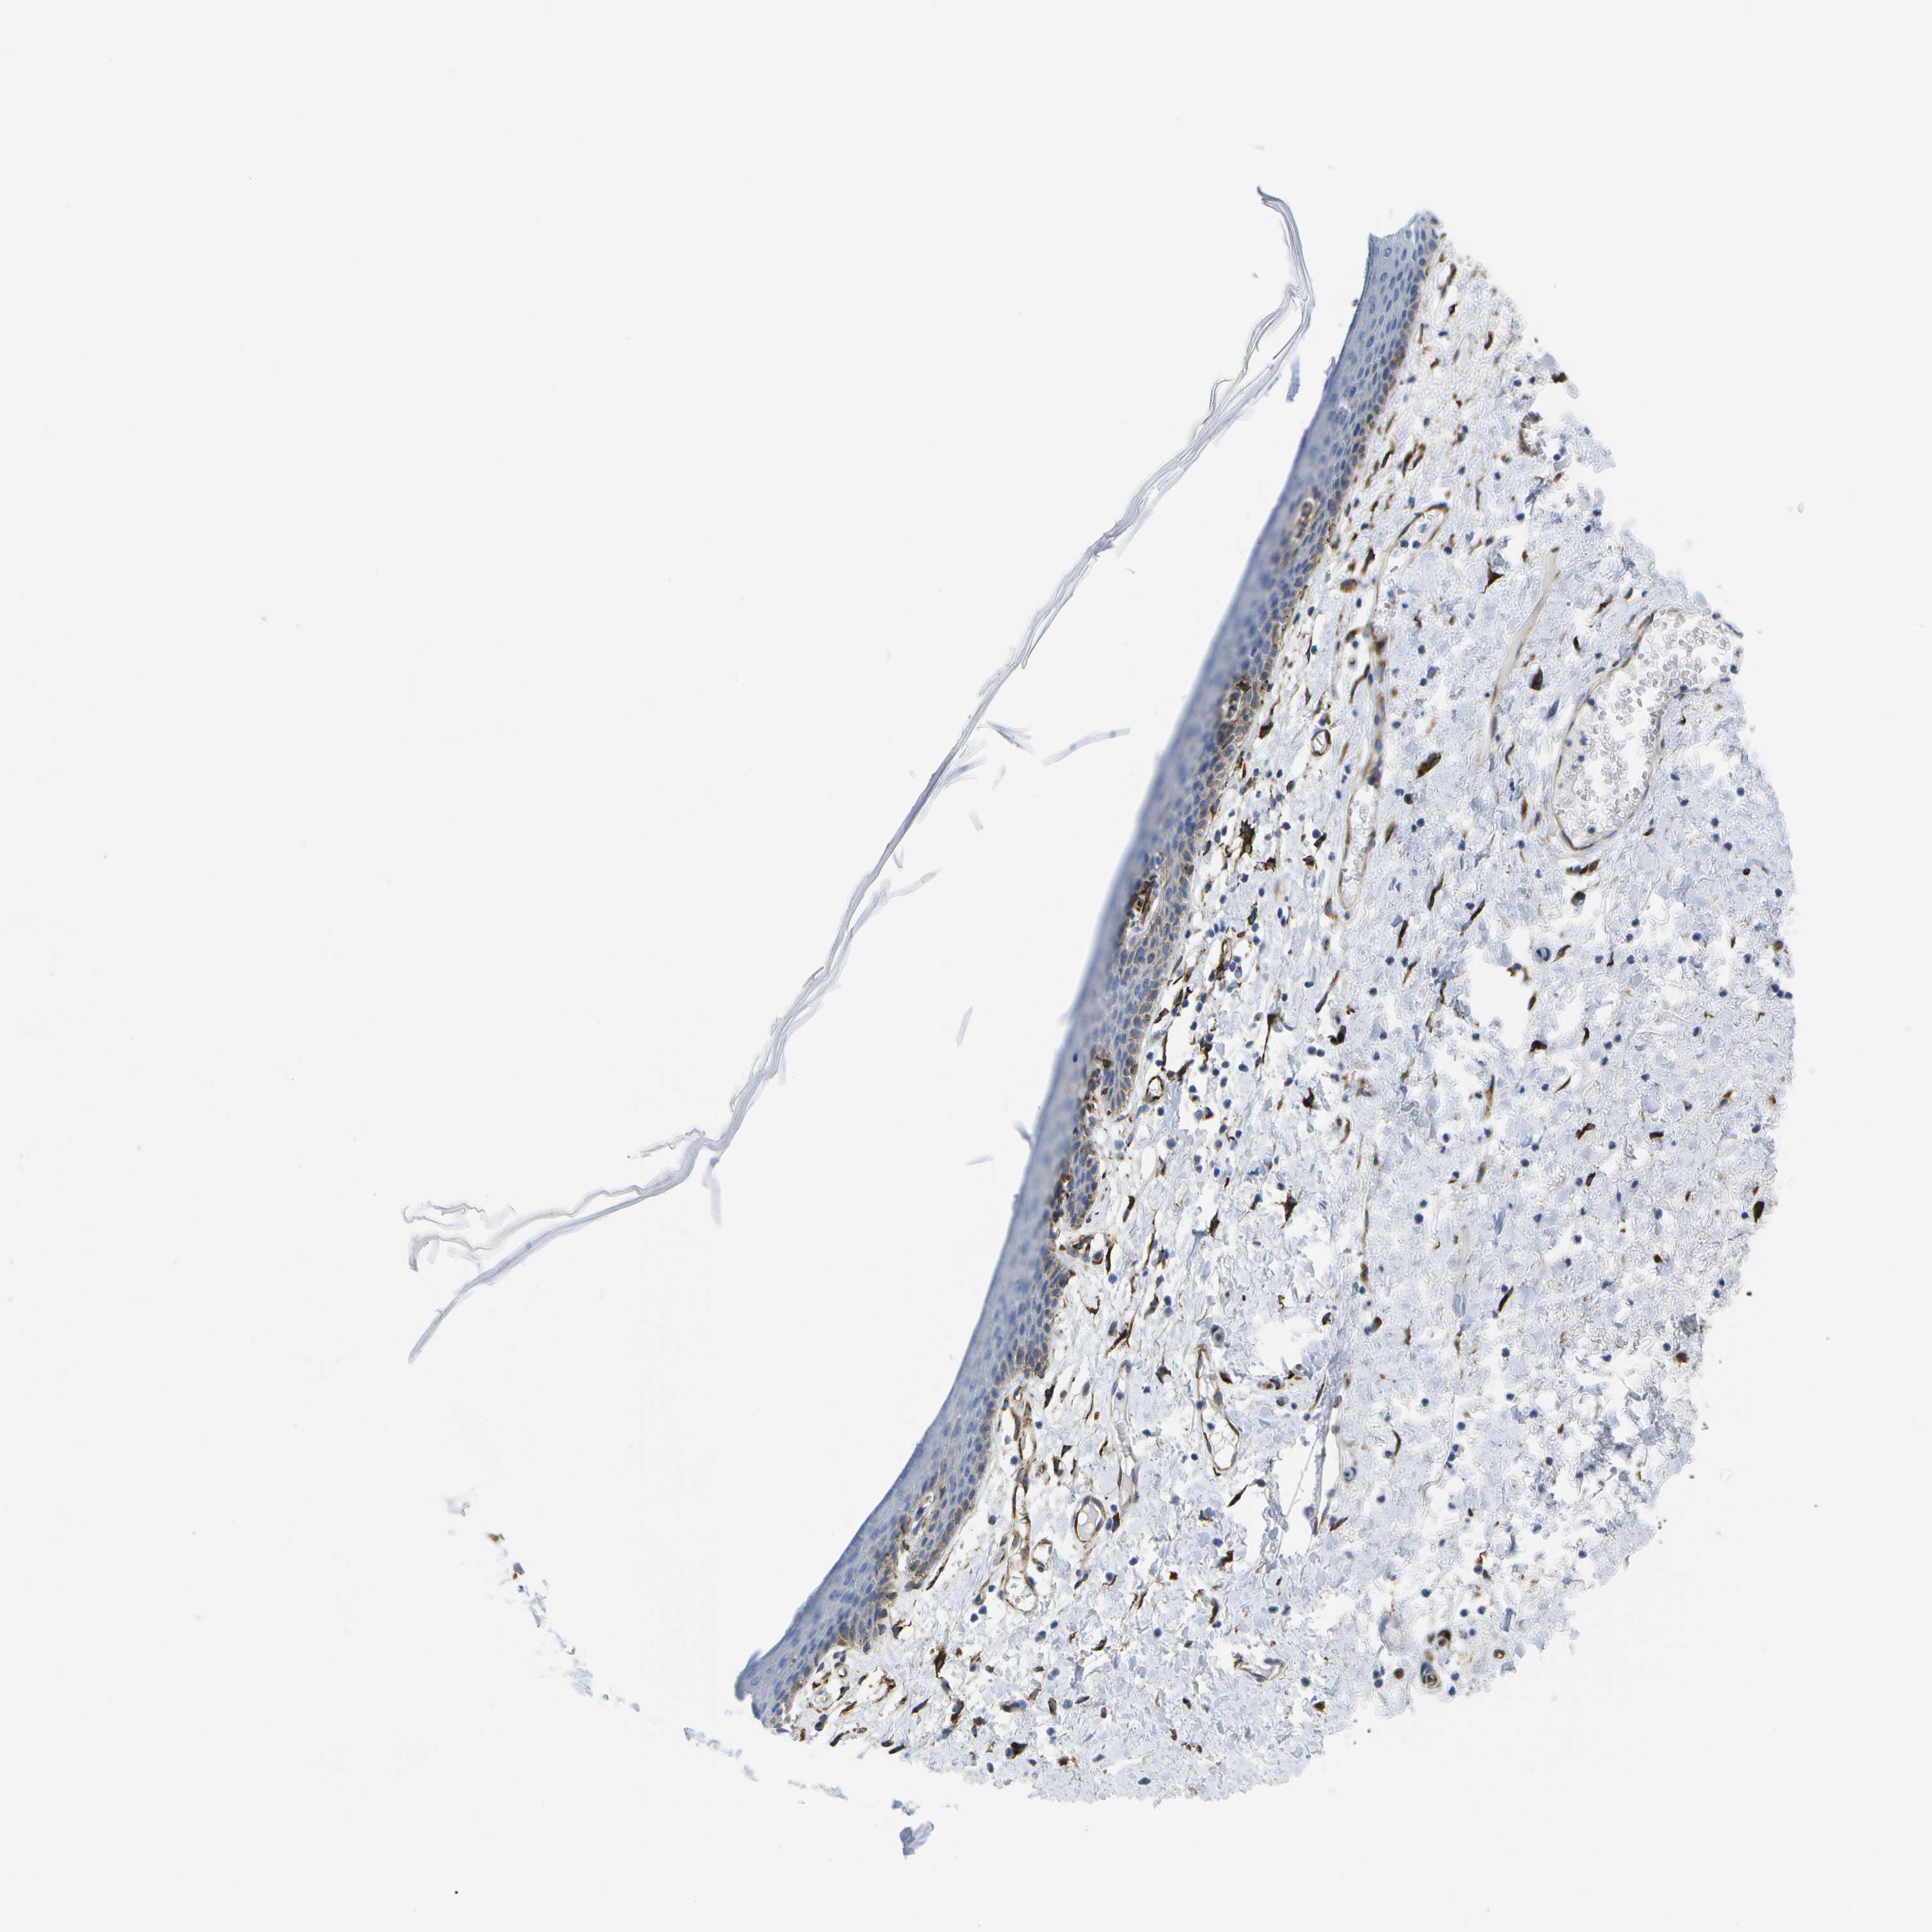

SKIN 1 - Antibody stainingi

Antibody staining in the annotated cell types in the current human tissue is reported as not detected, low, medium, or high, based on conventional immunohistochemistry profiling in selected tissues. This score is based on the combination of the staining intensity and fraction of stained cells.

Each image is clickable and will lead to virtual microscopy that enables deeper exploration of all samples and also displays staining intensity scores, fraction scores and subcellular localization as well as patient and tissue information for each sample.

Antibody HPA016807

Langerhans Not detected

Fibroblasts Medium

Keratinocytes Not detected

Melanocytes Not detected